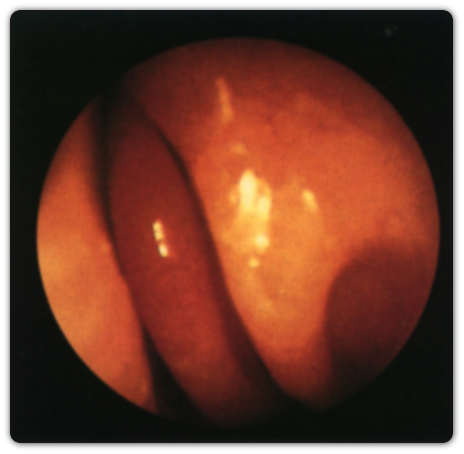

ΠΑΡΑΔΟΞΗ ΜΕΣΗ ΡΙΝΙΚΗ ΚΟΓΧΗ